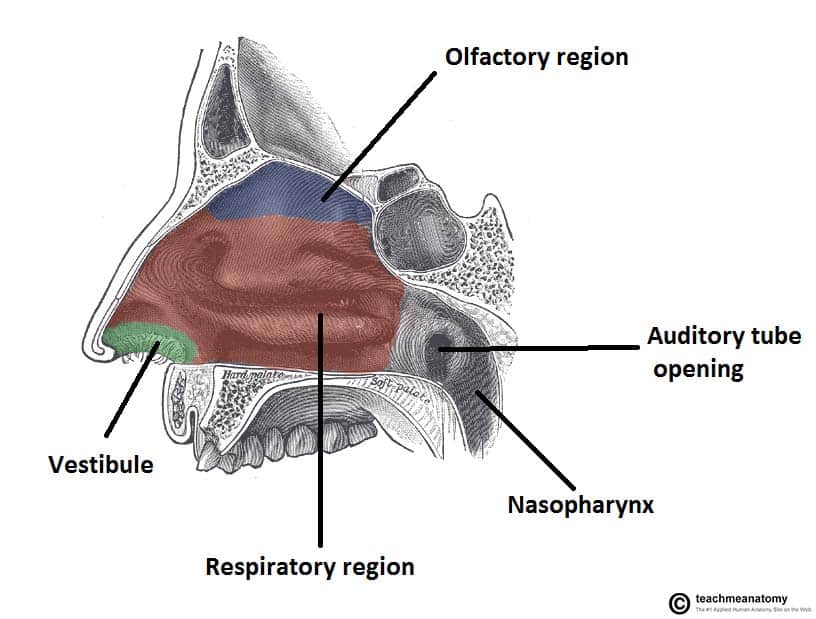

Projecting out of the lateral walls of the nasal cavity are curved shelves of bone. The flow of air from outside of the body to the lungs begins with the nose which is divided into the left and right nasal passages.

Nasal passage anatomy. Beyond the nasal valve the nasal passages are lined mostly by membranes more like the lining of the lungs called respiratory epithelium which is thin and rich in blood vessels. The sinuses are part of your nose and respiratory system. Openings into the nasal cavity.

The lateral nasal wall consists of inferior and middle turbinates and occasionally a superior or supreme turbinate bone. The turbinates consist of three ridges of thin shell like bone known as the nasal conchae. The nasal passages are lined with a membrane composed primarily of one layer of flat closely packed cells called epithelial cells.

Superior middle and inferior meatus. The nasal cavity extends from the external opening the nostrils. The nasal cavity is surrounded by a.

In bones behind your nose are your sphenoid sinuses. Anatomy of the nasal cavity. This region is divided into a labyrinth of slit like passages by multiple bony proturbances that fill the nose and act as shelves.

The exhaled air travels in the reverse path and leaves the body through the nasal cavity. The superior the middle and the inferior turbinates. Theyre lined with soft pink tissue called mucosa.

The nasal cavity divisions. As you breathe in air through your nose and. Anatomy of the nasal passages.

During inhalation air enters through the nostrils and passes via the nasal cavity into the pharynx and larynx the next sections in the respiratory tract to eventually reach the lungs. Anatomy and physiology of the nasal cavity inner nose and mucosa introduction. Anatomy of the nose.

The external nose consists of paired nasal bones and upper and lower lateral cartilages. The nasal cavity refers to the interior of the nose. The nasal cavity is the most superior part of the respiratory tract.